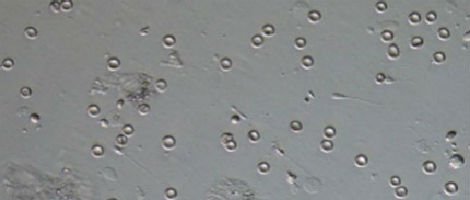

Para comprovar a fertilidade masculina o exame mais habitual é o espermograma. No âmbito deste exame uma amostra de sémen ejaculado do homem é recolhida e examinada em laboratório para que o número de espermatozóides possa ser contado e o seu estado analisado.

Azoospermia é definida como a ausência de espermatozóides no ejaculado. Calcula-se que, dentro dos problemas de infertilidade masculina, a azoospermia manifesta-se em entre 3 e 10% dos casos.

Existem dois tipos de azoospermia, a azoospermia secretora na qual os testículos não são capazes de produzir espermatozóides e a azoospermia obstrutiva, na qual existem espermatozóides que, devido a uma obstrução dos canais deferentes, não são expulsos no ejaculado.